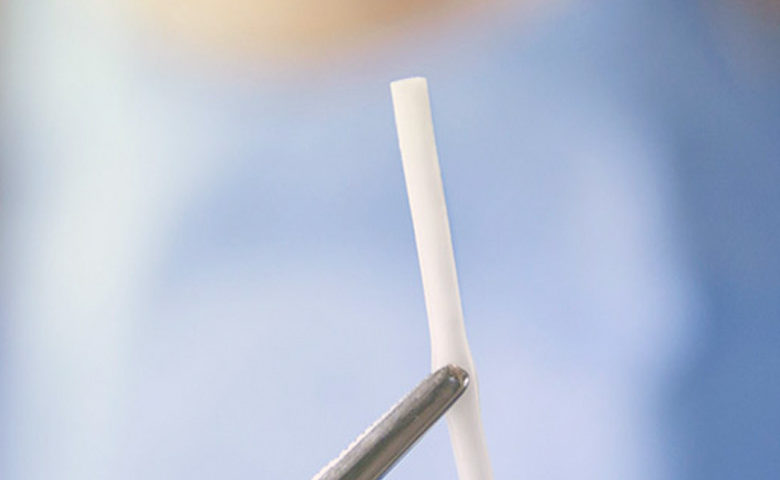

São tubinhos de Silicone, feitos com o mesmo material usado em próteses mamárias, cujas paredes possuem poros que permitem a passagem das moléculas de hormônios em doses diárias, durante um período pré-determinado de 6 meses a 1 ano.

Tantas vantagens em um tubinho de silicone de 4 cm: parece um milagre!